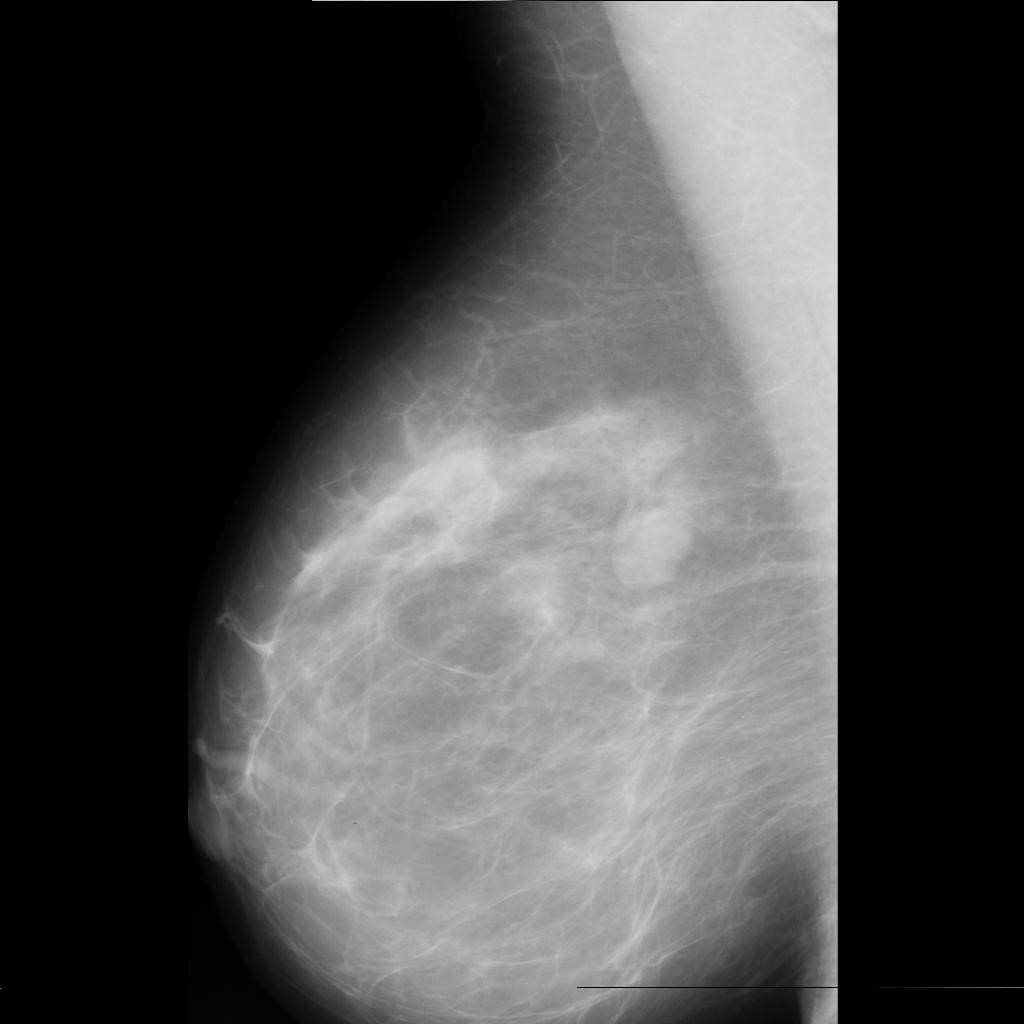

benign

malignant